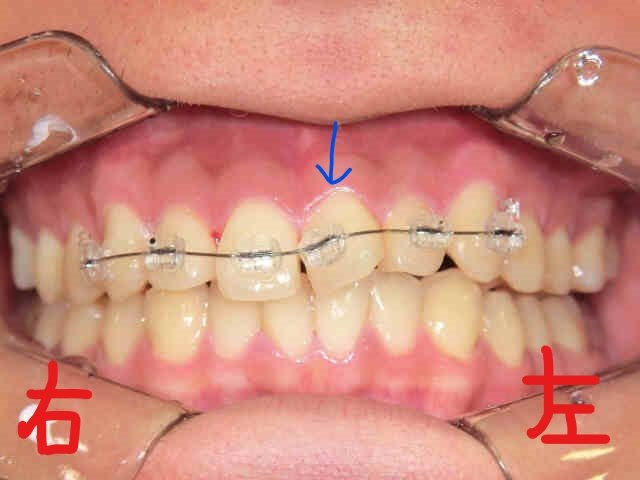

患者様は、左上の前歯(青色矢印)の“歪み(捻転)”を以前から気にされており、当院まで遠方よりご来院くださいました。

左上の写真は、上顎前歯にブラケット(ボタン)を装着した直後の状態、右上がブラケット装着前に上顎を下から見上げた写真です。主訴である左上の前歯がかなり捻転している様子がご確認いただけると思います。

次に、左上がブラケットを撤去する直前の上顎を下から見上げた写真、右上がブラケット撤去直後の写真です。青色矢印の歯にご注目ください。左上の前歯の捻転がしっかりと改善されているのがお分かりいただけると思います。